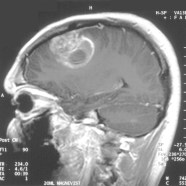

Glioblastoma (official name glioblastoma multiforme) is the most severe type of astrocytoma, identified by the appearance of rampant cell death (necrosis), abnormal appearance, rapid proliferation, and the formation of new blood vessels [4]. Not only is glioblastoma the most aggressive brain tumor, but it’s also among the most common, accounting for about 15% of all brain tumors and over half of all gliomas [3]. Within glioblastoma, tumors are categorized as either originating directly in the brain (“primary”) or starting elsewhere in the body and spreading to the brain (“secondary” or “metastatic”). Primary glioblastoma, the kind that took the life of John McCain, is by far the most prevalent and is particularly common in older individuals (median age 62 years), whereas secondary glioblastoma mainly manifests in younger adults (median age 44 years) [5].

Feature image: By Christaras A (Created myself from anonymized patient MR) [GFDL (http://www.gnu.org/copyleft/fdl.html), CC-BY-SA-3.0 (http://creativecommons.org/licenses/by-sa/3.0/) or CC BY 2.5 (https://creativecommons.org/licenses/by/2.5)%5D, via Wikimedia Commons